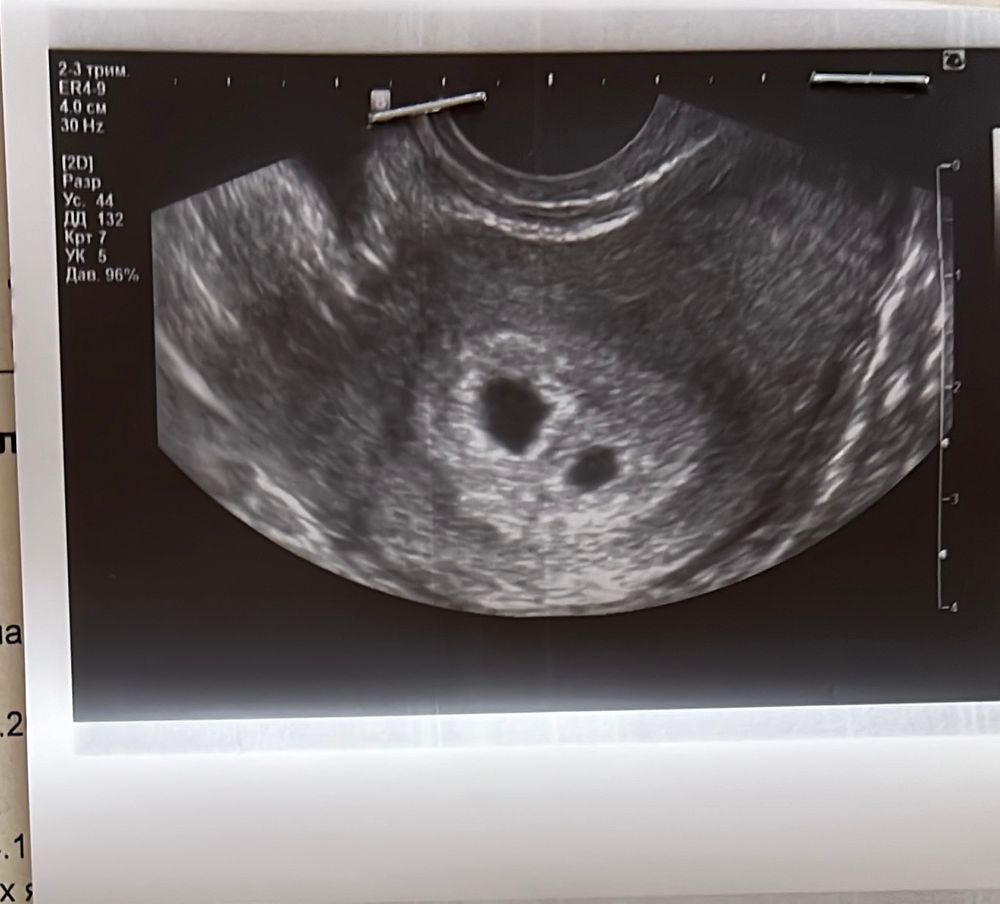

Мамочки двоен , у вас было отставание по первому узи ваших ПЯ и ЖМ? Я что-то сначала обрадовалась двум пузырикам , а потом зачем-то начала гуглить все остальное 🙈

У меня на сроке 5н3д (по дате последних м) и 3н 3д по дате эмбриональной -

1) ПЯ 10мм, ЖМ 2.4 мм

2) ПЯ 6,1 мм, ЖМ 1.7мм

Смущается разница, хотя муж убеждает что может быть ПЯ в разных чуть проекциях лежат на узи и поэтому так считывается размер . Короче переживаю, на узи только 21 числа пойду.